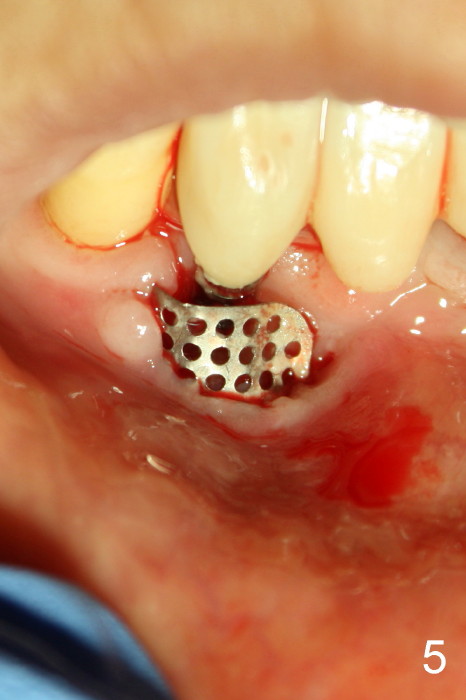

The patient has had chronic pain and swelling associated with the implant at the site of #26 (Fig.1). The extent of implant thread exposure is shown in Fig.2 after flap reflection; inflammatory granulation tissue is present around the most coronal threads (*, one year post cementation). Following debridement and Clindamycin soaking, allograft is placed around the exposed threads; a titanium mesh is used to contain the graft (Fig.3). The flap is closed with tension in spite of the periosteum being underscored. The patient develops moderate to severe ecchymosis postop.

The coronal portion of the mesh is exposed with loss of bone graft granules. It appears that the mesh has lost its function. It is planned to be removed. PA is taken 16 days post placement of the mesh (Fig.4).

Fig.5 is taken following local anesthesia to show the exposed mesh, 22 days post placement. When the latter is removed, the exposed threads appear to be less (Fig.6, as compared to Fig.2). There is healthy granulation tissue growth apically (*). The patient is asymptomatic 1 month post mesh removal; there is no tenderness around exposed threads (Fig.7). Connective tissue graft is planned to cover the exposed threads through tunnel technique. Thread exposure appears less 3 months post mesh removal (Fig.8). There is infection when the region is not kept clean (Fig.9 (2.5 years post mesh removal)). The other 1-piece implant should have minor implant exposure (<). It appears that there is no thread exposure associated with the immediate implant at #28. Using smaller 1-piece implants (2.5 or 2.0 vs. 3 mm) with flap surgery should be able to prevent the complication. The 72-year-old phobic patient declines any further treatment. Two years later, she agrees to have treatment because of repeated infection (Fig.10). Impression has been taken for stent. After sectioning FPD and removing the infected implant (Tatum), a smaller implant will be placed in between the implants. If her vein is not too small, blood will be drawn for PRF.